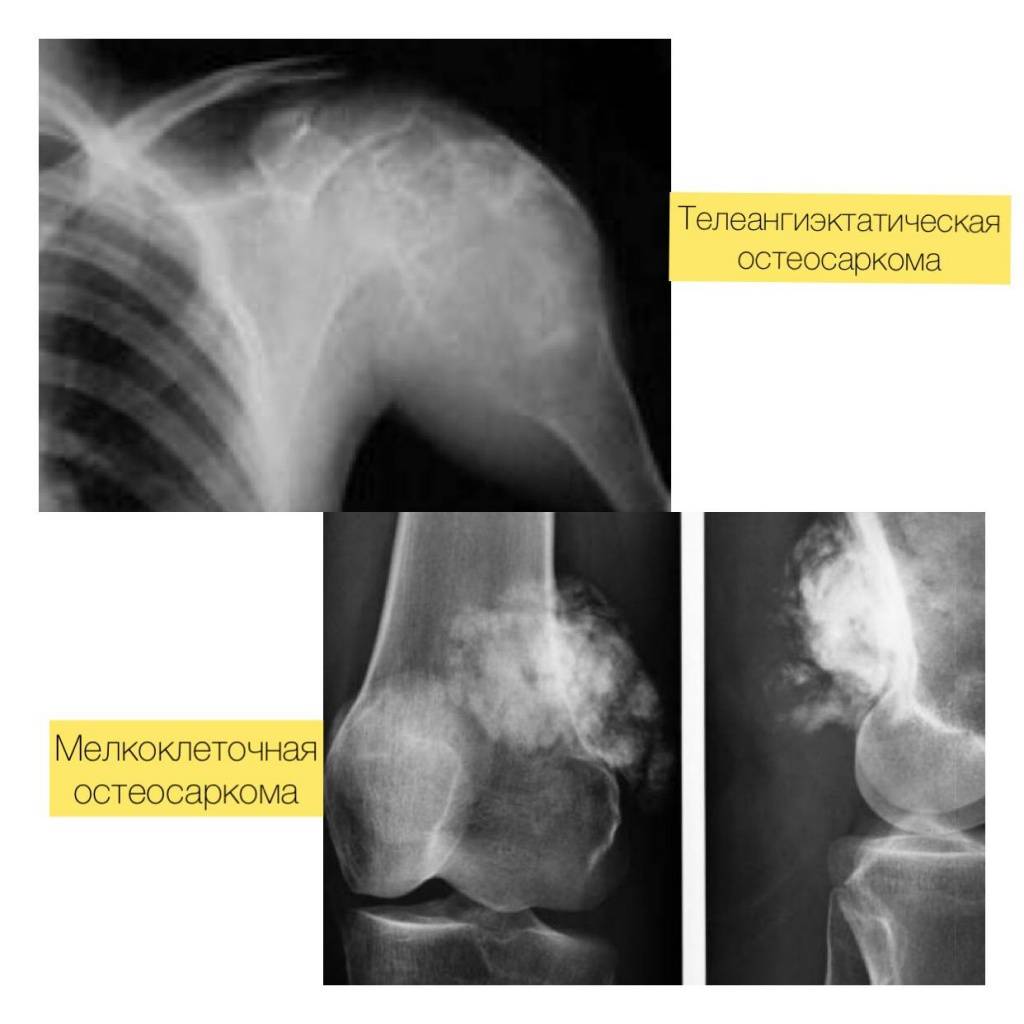

Телеангиэктатическая остеосаркома – новообразование имеет полости, часть из которых заполнена кровянистым содержимым. Это делает их похожими на аневризмальные кисты. Дифференциальным признаком выступает наличие многоядерных клеток, отсутствующих в кистозных образованиях. Между полостями опухоли обнаруживаются многочисленные мелкие низкодифференцированные клетки.

Мелкоклеточная – образована мелкими клетками округлой формы, из-за чего сходна с саркомой Юинга. Но содержит остеоид.